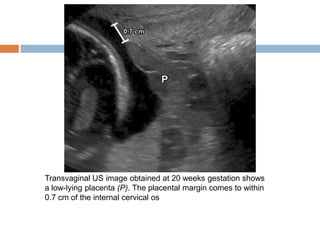

Placenta Previa

   Placenta previa refers to abnormal

implantation of the placenta in the lower

uterine segment, overlying or near the internal

cervical os

   Normally, the lower placental edge should be

at least 2 cm from the margin of the internal

cervical os.

   The diagnosis of placenta previa should not be

made before 15 weeks gestation.

Transvaginal US image obtained at 20 weeks gestation shows

a low-lying placenta (P). The placental margin comes to within

0.7 cm of the internal cervical os

Transvaginal US imageobtained at 20 weeks gestation shows a low-lying placenta (P). The placental margin comes to within 0.7 cm of the internal cervical os